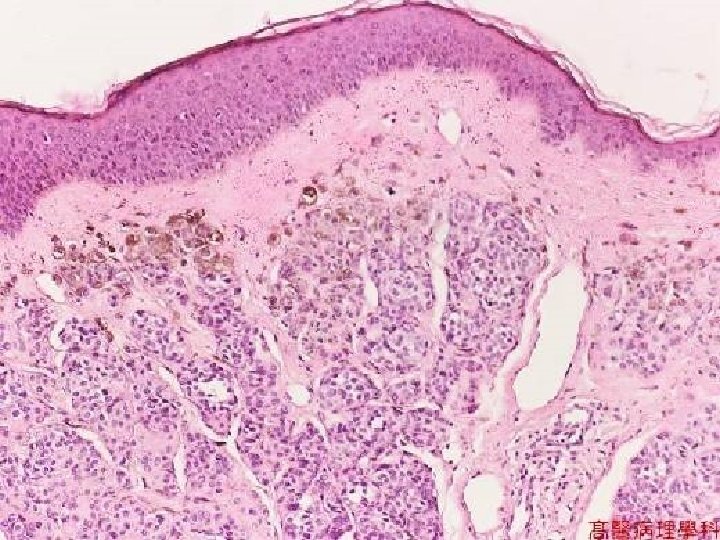

MALIGNANT MELANOMA • Incidence rising, VERY much • Related to SUN like ALL skin cancers are • The only primary skin cancer that can kill you (except for the RARE Merkel cell tumor) • QUICKLY METASTASIZES • Has both VERTICAL and HORIZONTAL growth phase but prognosis is 100% related to the VERTICAL, (BRESLOW staging, TNM too) • DIFFICULT to differentiate from NEVUS clinically and often microscopically

NEVI • Many, many adjectives and classifications. • The MAIN things to differentiate from melanomas • Junctional (more pigmented, more closely associated with melanoma) • Intradermal • Compound (both)